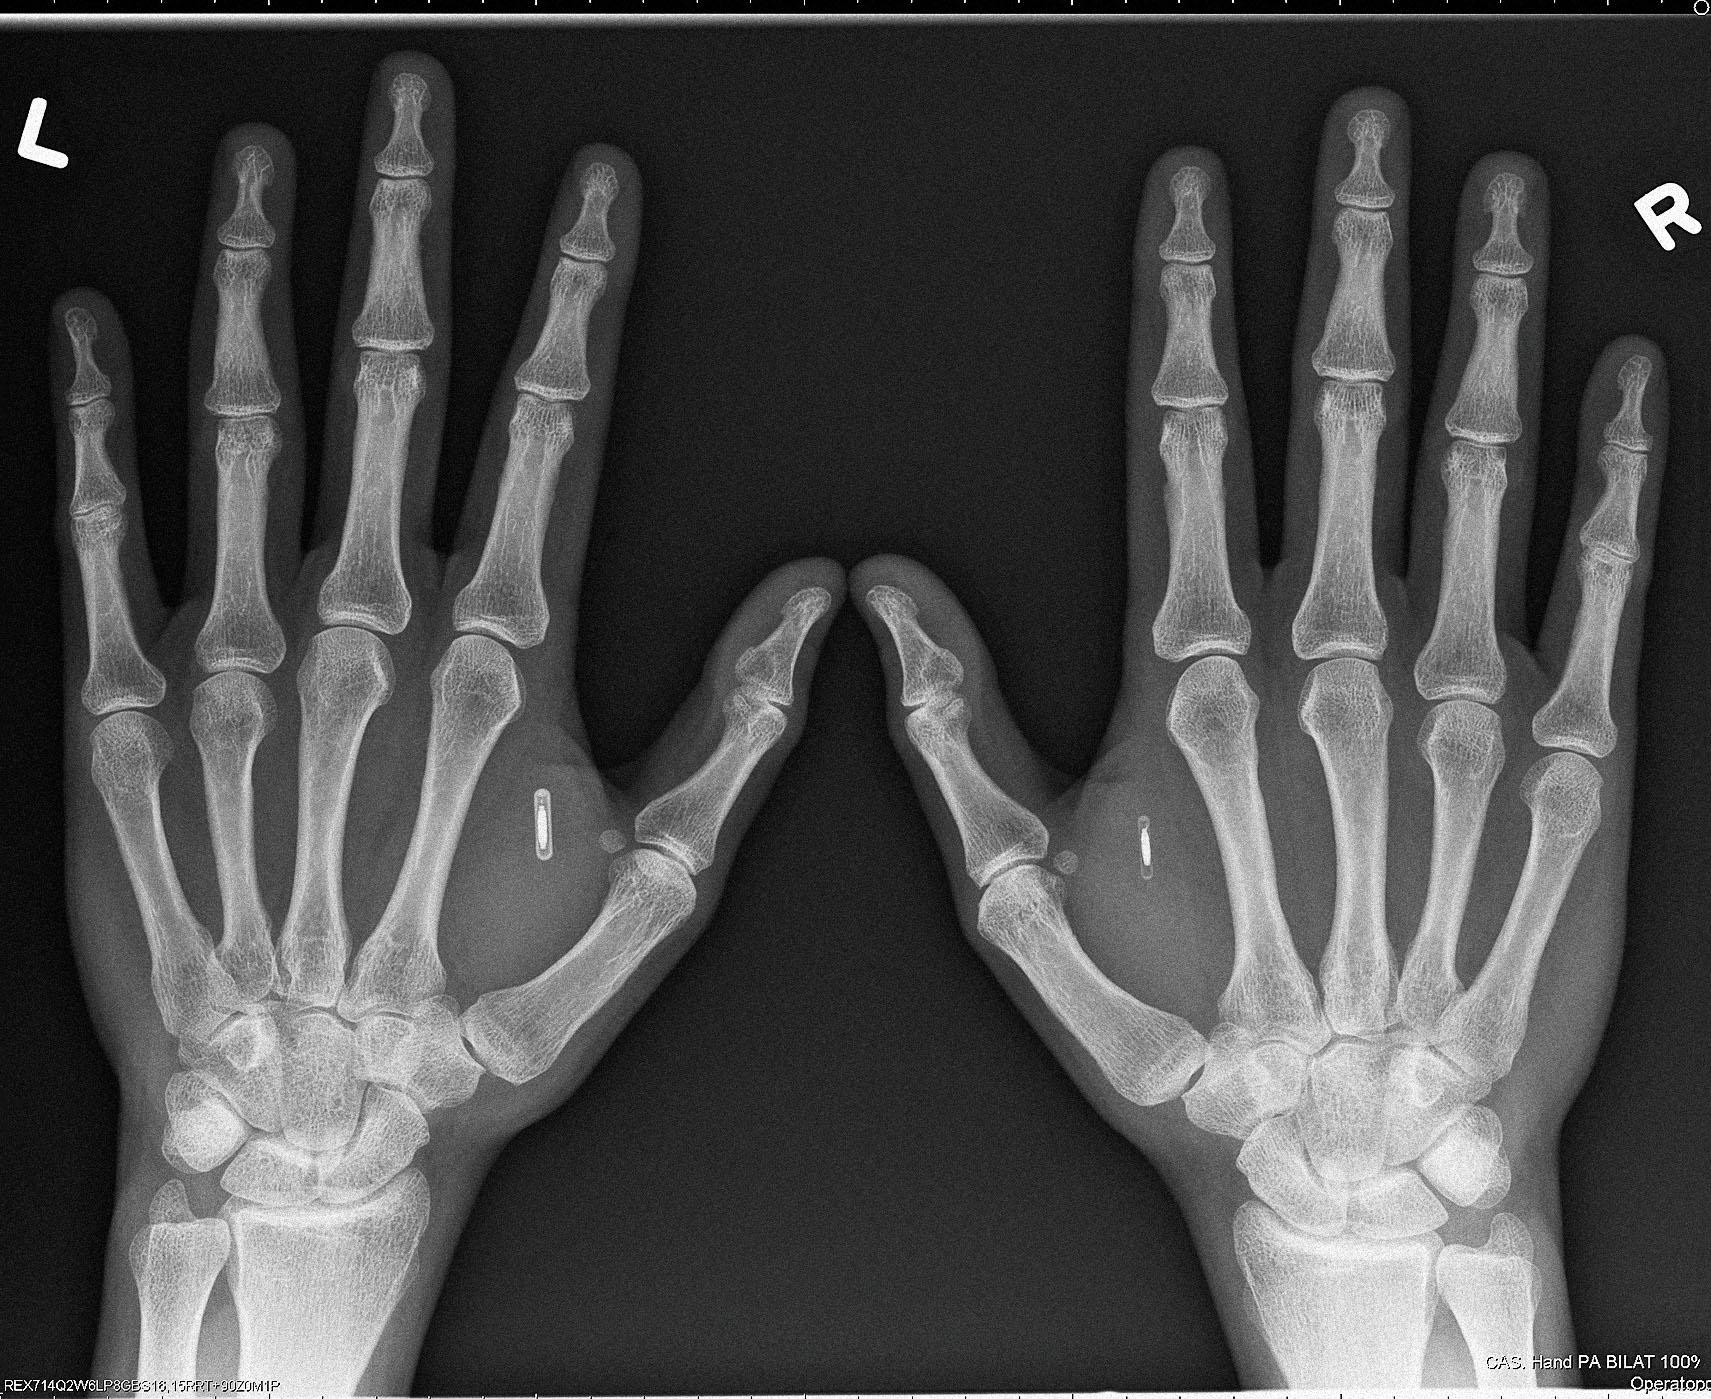

Бывший IT-консультант из Сиэтла Амаль Граафстра носит под кожей четыре NFC- и RFID-чипа собственной разработки и продает тысячи таких же девайсов «киборгам»энтузиастам по всему миру, в том числе в России. Журнал РБК узнал у основателя компании Dangerous Things, как устроен бизнес по «роботизации» людей и зачем его клиенты вживляют в себя «умные» импланты

Все началось в 2005 году. «Я тогда работал в IT-консалтинге медицинских учреждений, часто засиживался в офисе допоздна и при этом постоянно забывал ключи. Чтобы не запирать себя, придумал такую альтернативу — вживить под кожу чип». Технологию операции он почерпнул у ветеринаров, которые чипируют домашних животных при помощи специальной иглы. Чипы для питомцев Граафстре не подошли: девайсы производятся из материалов, которые человеческий организм может отторгнуть. Граафстра решил собрать чип самостоятельно. Детали, не вызывающие аллергии, он заказал в интернете, а первый чип собрал дома. Он остановился на технологии беспроводной передачи данных NFC, сегодня встроенной в большинство смартфонов: «Я сразу понял, что за ней — будущее. NFC-чипы тогда еще никто массово не производил и уж тем более не вживлял в себя».

Цена на чипы разнится в зависимости от серии. Серия X — самые популярные из-за простоты установки NFC- и RFID-транспондеры. Их Dangerous Things продает по $79, они не требуют подзарядки и способны нести информацию о пользователе, его электронные ключи. Следующая серия — Flex. Это чип в гибком биополимере стоимостью $200. Если девайсы серии X можно вживить только под кожу между большим и указательным пальцем «ветеринарной» иглой с чуть увеличенным диаметром, то Flex размещаются чуть выше запястья, а их «установка» требует небольшой хирургической операции.